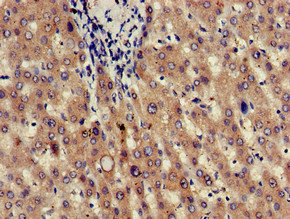

JAG1 Antibody (CSB-PA01949A0Rb)

驗證數(shù)據(jù)

Immunohistochemistry of paraffin-embedded human liver tissue using CSB-PA01949A0Rb at dilution of 1:100